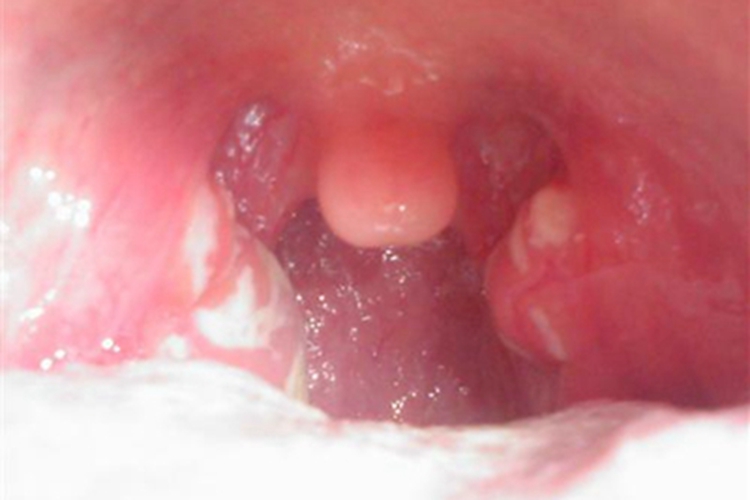

鼻咽炎患者可有黏膜损害,表现为患者局部出现突出黏膜的红肿包块,对称分布多呈圆形,大小相似,其上附有略厚的黄白色假膜,边界清晰,形状不规则,伴有鼻咽干燥感。